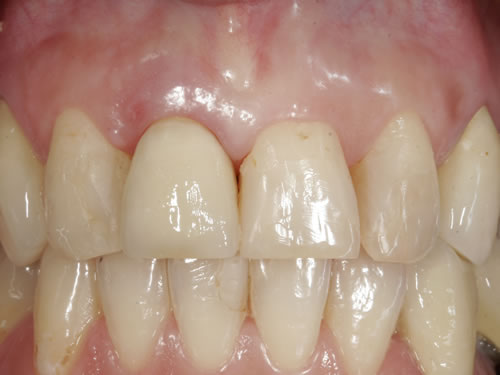

Häufig führt ein Zahnverlust zu einem Verlust von Knochen (Hartgewebe) und der bedeckenden Schleimhaut (Weichgewebe). Besonders im sichtbaren ästhetisch sensiblen Bereich ist es aber notwendig, dass sowohl Hart- als auch Weichgewebe so wiederhergestellt wird, dass im Idealfall das Zahnimplantat mit seiner Krone dem Aussehen des ehemaligen gesunden Zahn entspricht. Als Erfolgskriterien werden aus zahntechnischer Sicht die Form, Farbe und Größe der individuellen Krone angesehen. Aus medizinischer Sicht gibt es wichtige Erfolgskriterien, die die Implantatposition, die Implantatlänge, den Implantatdurchmesser, den Zahnfleischrand im Vergleich zum Nachbarzahn und die Zahnfleischpapillen zwischen den Zähnen beinhalten. Zusätzlich braucht man ein zahntechnisches Labor, das mit der Keramikverarbeitung ein natürliches Aussehen gestalten kann. Nur, wenn alle Parameter perfekt sind, ist das Ergebnis perfekt. Das macht den Einzelzahnersatz im Oberkieferfrontzahngebiet zu einer echten Herausforderung.

Nach der Entfernung von Zähnen kommt es schnell zu Knochenverlust (Resorptionen) und entsprechendem Verlust von Schleimhaut. Die Schleimhaut kann durch bestimmte Operationstechniken wiederhergestellt werden, in dem man freie oder gestielte Bindegewebstransplantate z. B. vom Gaumen entnimmt und das fehlende Material so ersetzt. Das Weichgewebe kann in unterschiedlichen Behandlungsphasen korrigiert werden. In vielen Fällen wird es während der Implantation oder bei der Freilegung verbessert. Manchmal müssen Feinkorrekturen auch nach Eingliederung der fertig gestellten Krone erfolgen, wenn ästhetische Einbußen vorliegen. Häufig hat die Zahnfleischkorrektur auch noch einmal die Änderung der endgültigen Krone zur Folge (Abb. 7.14, 7.15).

Abb. 7.14: Unbefriedigendes ästhetisches Ergebnis nach Implantatversorgung.

Abb. 7.15: Perfektes Ergebnis nach Weichgewebskorrektur und nach Eingliederung der geänderten Krone.